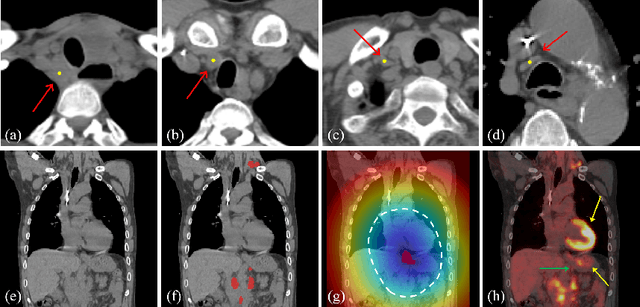

Abstract:Determining the spread of GTV$_{LN}$ is essential in defining the respective resection or irradiating regions for the downstream workflows of surgical resection and radiotherapy for many cancers. Different from the more common enlarged lymph node (LN), GTV$_{LN}$ also includes smaller ones if associated with high positron emission tomography signals and/or any metastasis signs in CT. This is a daunting task. In this work, we propose a unified LN appearance and inter-LN relationship learning framework to detect the true GTV$_{LN}$. This is motivated by the prior clinical knowledge that LNs form a connected lymphatic system, and the spread of cancer cells among LNs often follows certain pathways. Specifically, we first utilize a 3D convolutional neural network with ROI-pooling to extract the GTV$_{LN}$'s instance-wise appearance features. Next, we introduce a graph neural network to further model the inter-LN relationships where the global LN-tumor spatial priors are included in the learning process. This leads to an end-to-end trainable network to detect by classifying GTV$_{LN}$. We operate our model on a set of GTV$_{LN}$ candidates generated by a preliminary 1st-stage method, which has a sensitivity of $>85\%$ at the cost of high false positive (FP) ($>15$ FPs per patient). We validate our approach on a radiotherapy dataset with 142 paired PET/RTCT scans containing the chest and upper abdominal body parts. The proposed method significantly improves over the state-of-the-art (SOTA) LN classification method by $5.5\%$ and $13.1\%$ in F1 score and the averaged sensitivity value at $2, 3, 4, 6$ FPs per patient, respectively.

Abstract:Finding, identifying and segmenting suspicious cancer metastasized lymph nodes from 3D multi-modality imaging is a clinical task of paramount importance. In radiotherapy, they are referred to as Lymph Node Gross Tumor Volume (GTVLN). Determining and delineating the spread of GTVLN is essential in defining the corresponding resection and irradiating regions for the downstream workflows of surgical resection and radiotherapy of various cancers. In this work, we propose an effective distance-based gating approach to simulate and simplify the high-level reasoning protocols conducted by radiation oncologists, in a divide-and-conquer manner. GTVLN is divided into two subgroups of tumor-proximal and tumor-distal, respectively, by means of binary or soft distance gating. This is motivated by the observation that each category can have distinct though overlapping distributions of appearance, size and other LN characteristics. A novel multi-branch detection-by-segmentation network is trained with each branch specializing on learning one GTVLN category features, and outputs from multi-branch are fused in inference. The proposed method is evaluated on an in-house dataset of $141$ esophageal cancer patients with both PET and CT imaging modalities. Our results validate significant improvements on the mean recall from $72.5\%$ to $78.2\%$, as compared to previous state-of-the-art work. The highest achieved GTVLN recall of $82.5\%$ at $20\%$ precision is clinically relevant and valuable since human observers tend to have low sensitivity (around $80\%$ for the most experienced radiation oncologists, as reported by literature).

Abstract:Finding and identifying scatteredly-distributed, small, and critically important objects in 3D oncology images is very challenging. We focus on the detection and segmentation of oncology-significant (or suspicious cancer metastasized) lymph nodes (OSLNs), which has not been studied before as a computational task. Determining and delineating the spread of OSLNs is essential in defining the corresponding resection/irradiating regions for the downstream workflows of surgical resection and radiotherapy of various cancers. For patients who are treated with radiotherapy, this task is performed by experienced radiation oncologists that involves high-level reasoning on whether LNs are metastasized, which is subject to high inter-observer variations. In this work, we propose a divide-and-conquer decision stratification approach that divides OSLNs into tumor-proximal and tumor-distal categories. This is motivated by the observation that each category has its own different underlying distributions in appearance, size and other characteristics. Two separate detection-by-segmentation networks are trained per category and fused. To further reduce false positives (FP), we present a novel global-local network (GLNet) that combines high-level lesion characteristics with features learned from localized 3D image patches. Our method is evaluated on a dataset of 141 esophageal cancer patients with PET and CT modalities (the largest to-date). Our results significantly improve the recall from $45\%$ to $67\%$ at $3$ FPs per patient as compared to previous state-of-the-art methods. The highest achieved OSLN recall of $0.828$ is clinically relevant and valuable.